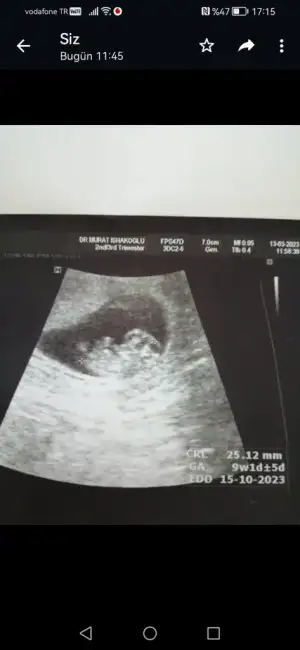

sandriyon tahminlerinizi alayım tatlımlar karından çekildim bugün çok fotojenik değil miyiz ama

ne guzel buyumus bebısler goruyoruz :) kız annesı :)Papatyamaviss bugun 9+1 günlüğüz kontrolden geldik.teyzesi bizede bi cinsiyet tahmininde bulunurmusun